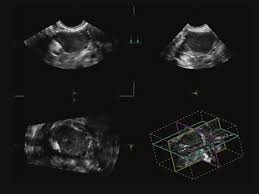

Toshiba Xario™ XG je barevný ultrazvukový systém se sdílenými službami Doppler, který kombinuje vynikající kvalitu obrazu s ergonomickým designem. Tento všestranný přístroj je vybaven řadou pokročilých funkcí, které zajišťují konzistentní poskytování vysoce kvalitních snímků v širokém spektru klinických aplikací, včetně břicha, prsou, malých částí, štítné žlázy a specializovaných OB/GYN aplikací s 3D/4D zobrazením.

- 3D/4D možnosti: Pokročilé zobrazení pro OB/GYN aplikace.